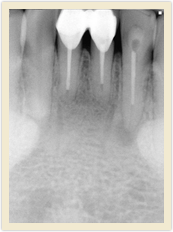

![]() |

| Before Photo | After Photo |